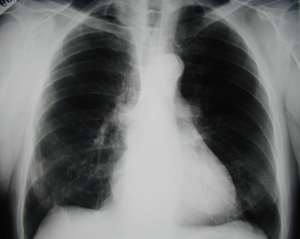

Εικόνα 1

Οπισθιοπρόσθια ακτινογραφία θώρακος που δείχνει όγκο στο δεξιό άνω λοβό.